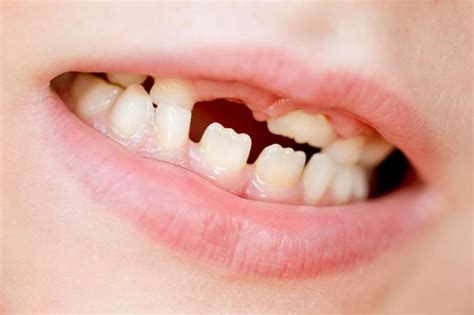

No es muy raro ver niños a partir de 6 o 7 años cuyos dientes recién salidos tienen el borde de los dientes en forma de sierra. A estos dientes en forma de serrucho se les conocen como mamelones.

Los mamelones dentales son protuberancias de esmalte y dentina. Cada diente tiene 3 mamelones dentales, ¿te has fijado? Estos bultitos se forman durante la calcificación de la corona dentro del saco dentario. Y aparecen a los 6-7 años de edad cuando empieza la erupción de los permanentes.

La forma serrada, llamada mamelón, ya se forma en el saco dentario antes de salir y, una vez erupcionado el diente, la forma desaparece a través de la masticación, el cortar con los dientes, la fricción de los dientes y con el mismo cepillado. Para quedarte tranquilo, los dientes en forma de sierra NO son un problema.

¿Por qué los dientes salen con picos?

Algunos padres se preocupan cuando a sus hijos les aparecen los dientes definitivos con una especie de “montañitas” en el borde de los mismos, por lo que mencionan que les han aparecido con picos. Estos nuevos dientes que consideramos raros si los comparamos con los demás, son normales y técnicamente se conocen como “mamelones incisales”, por lo que, en relación a este tema, no hay de qué preocuparse.